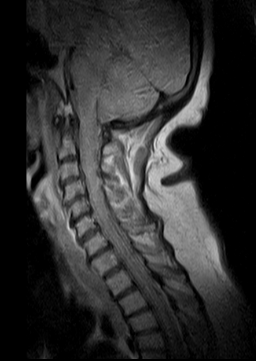

Trabalhamos com ressonâncias magnéticas coluna, podendo obter um diagnóstico preciso do quadro do paciente, com tempo para iniciar o tratamento adequado. Em caso de dúvidas, entre em contato com a nossa experiente e dedicada equipe de especialistas.